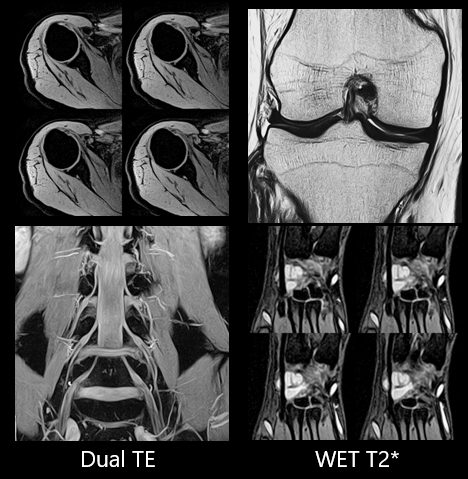

Пригнічення сигналу від жиру і візуалізація деталей кісток забезпечується оптимальною комбінацією Vantage Elan і 16-канальної котушки Flex SPEEDER™.